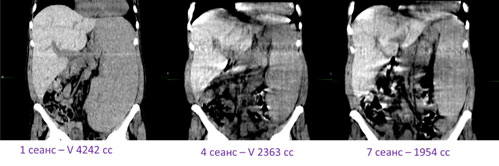

Пример адаптивной лучевой терапии при сленомегалии, обусловленной миелофиброзом. Регресс объема селезенки – 50% к седьмому сеансу. |